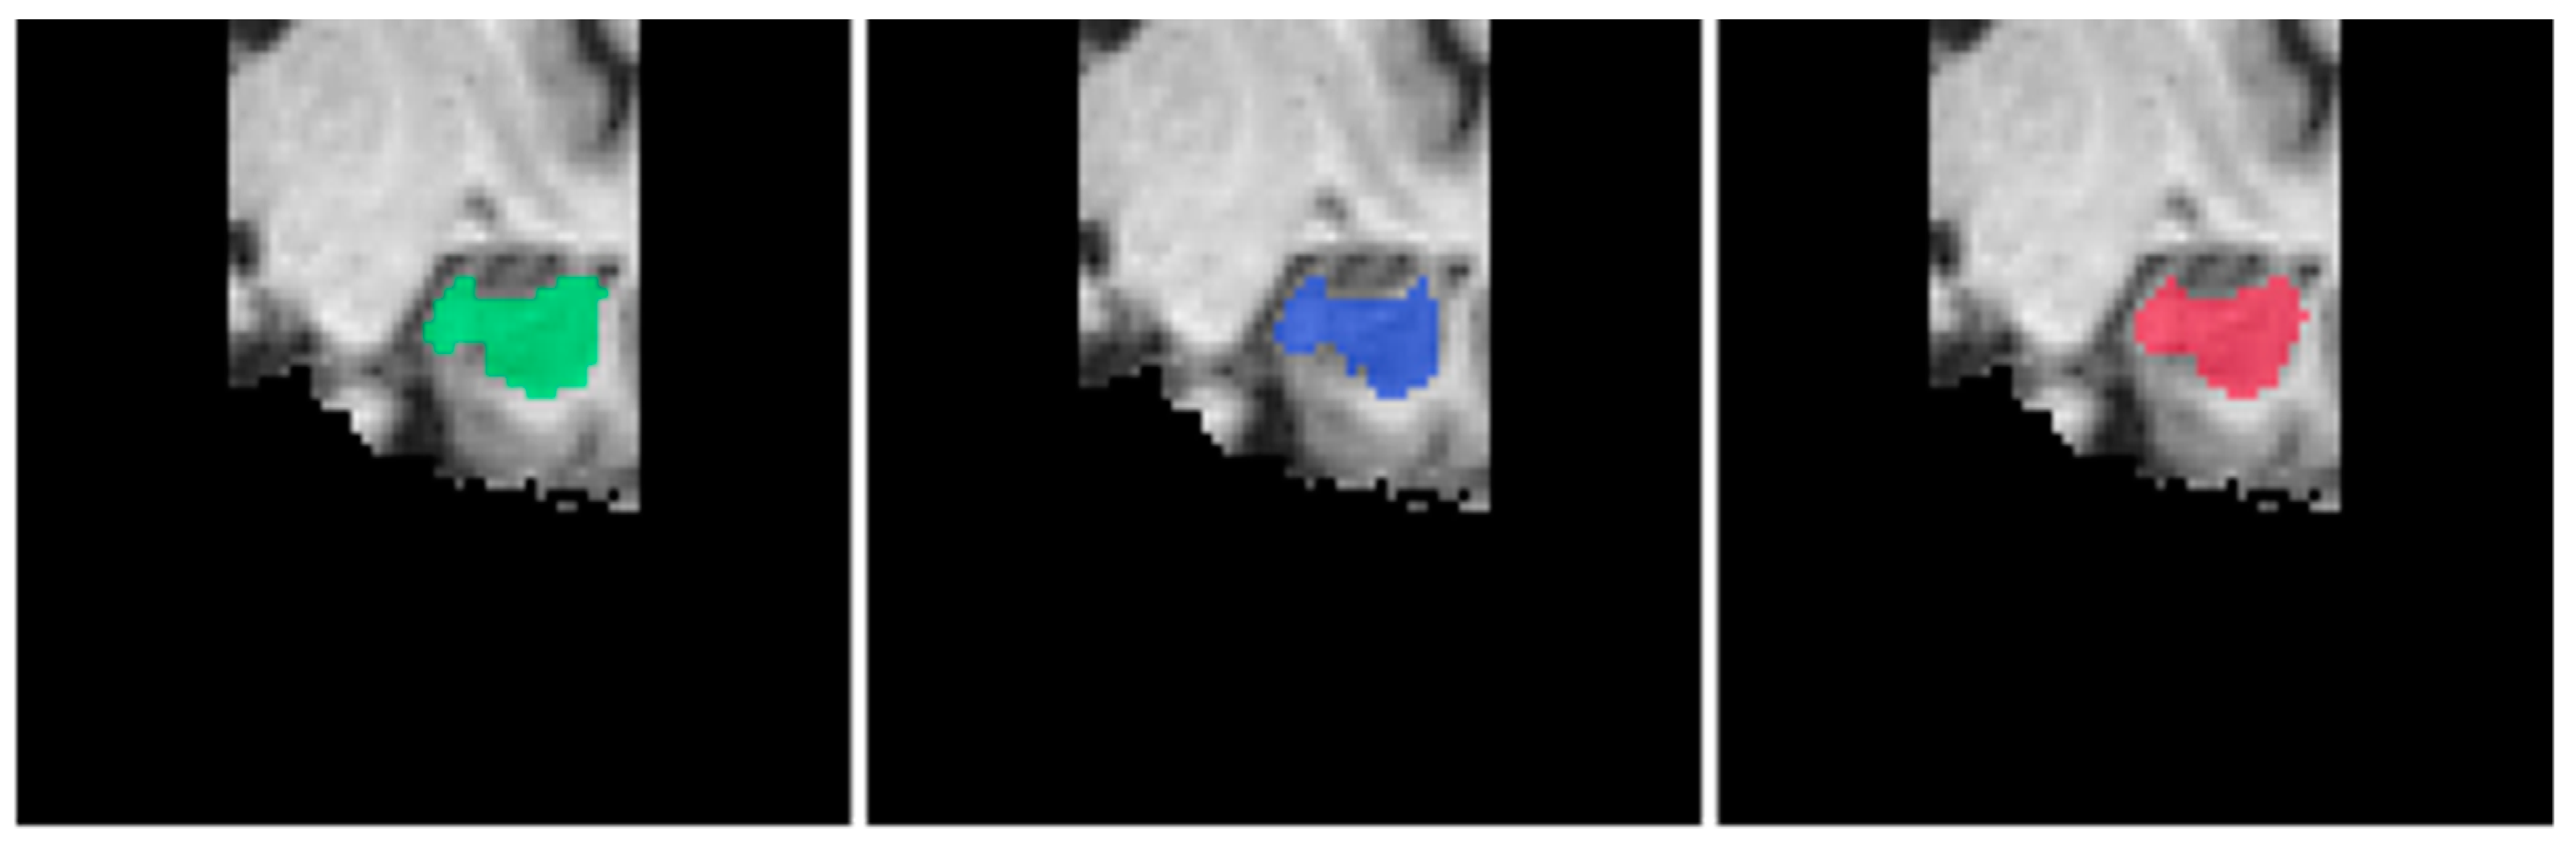

| Ensemble Model | Constituent 2D Models | Hippocampus | View |

|---|---|---|---|

| EnsembleUSegNetL | U-Seg-NetL0 U-Seg-NetLl U-Seg-NetL2 | Left Left Left | Sagittal Coronal Axial |

| EnsembleUSegNetR | U-Seg-NetR0 U-Seg-NetR1 U-Seg-NetR2 | Right Right Right | Sagittal Coronal Axial |